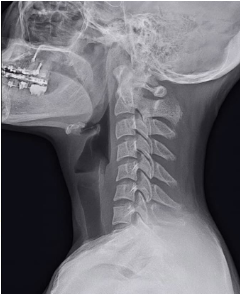

O sistema auditivo integra aferências somatossensoriais do trigêmeo e das raízes cervicais superiores já no núcleo coclear dorsal. Clinicamente, movimentos cervicais, mandibulares, posturais, respiratórios ou oculares podem modular o zumbido. Esse fenômeno, frequentemente tratado como subtipo etiológico, pode ter maior relevância prognóstica.

Propõe-se incorporar a modulação somatossensorial como variável prognóstica, investigando sua presença por história clínica e testes padronizados (movimentos cervicais, mandibulares, oculares, entre outros). Com base nisso, podem-se definir três perfis: zumbido não modulável (maior chance de habituação), parcialmente modulável (habituação mais lenta) e fortemente modulável (baixa taxa de habituação espontânea, com necessidade de intervenção direcionada).